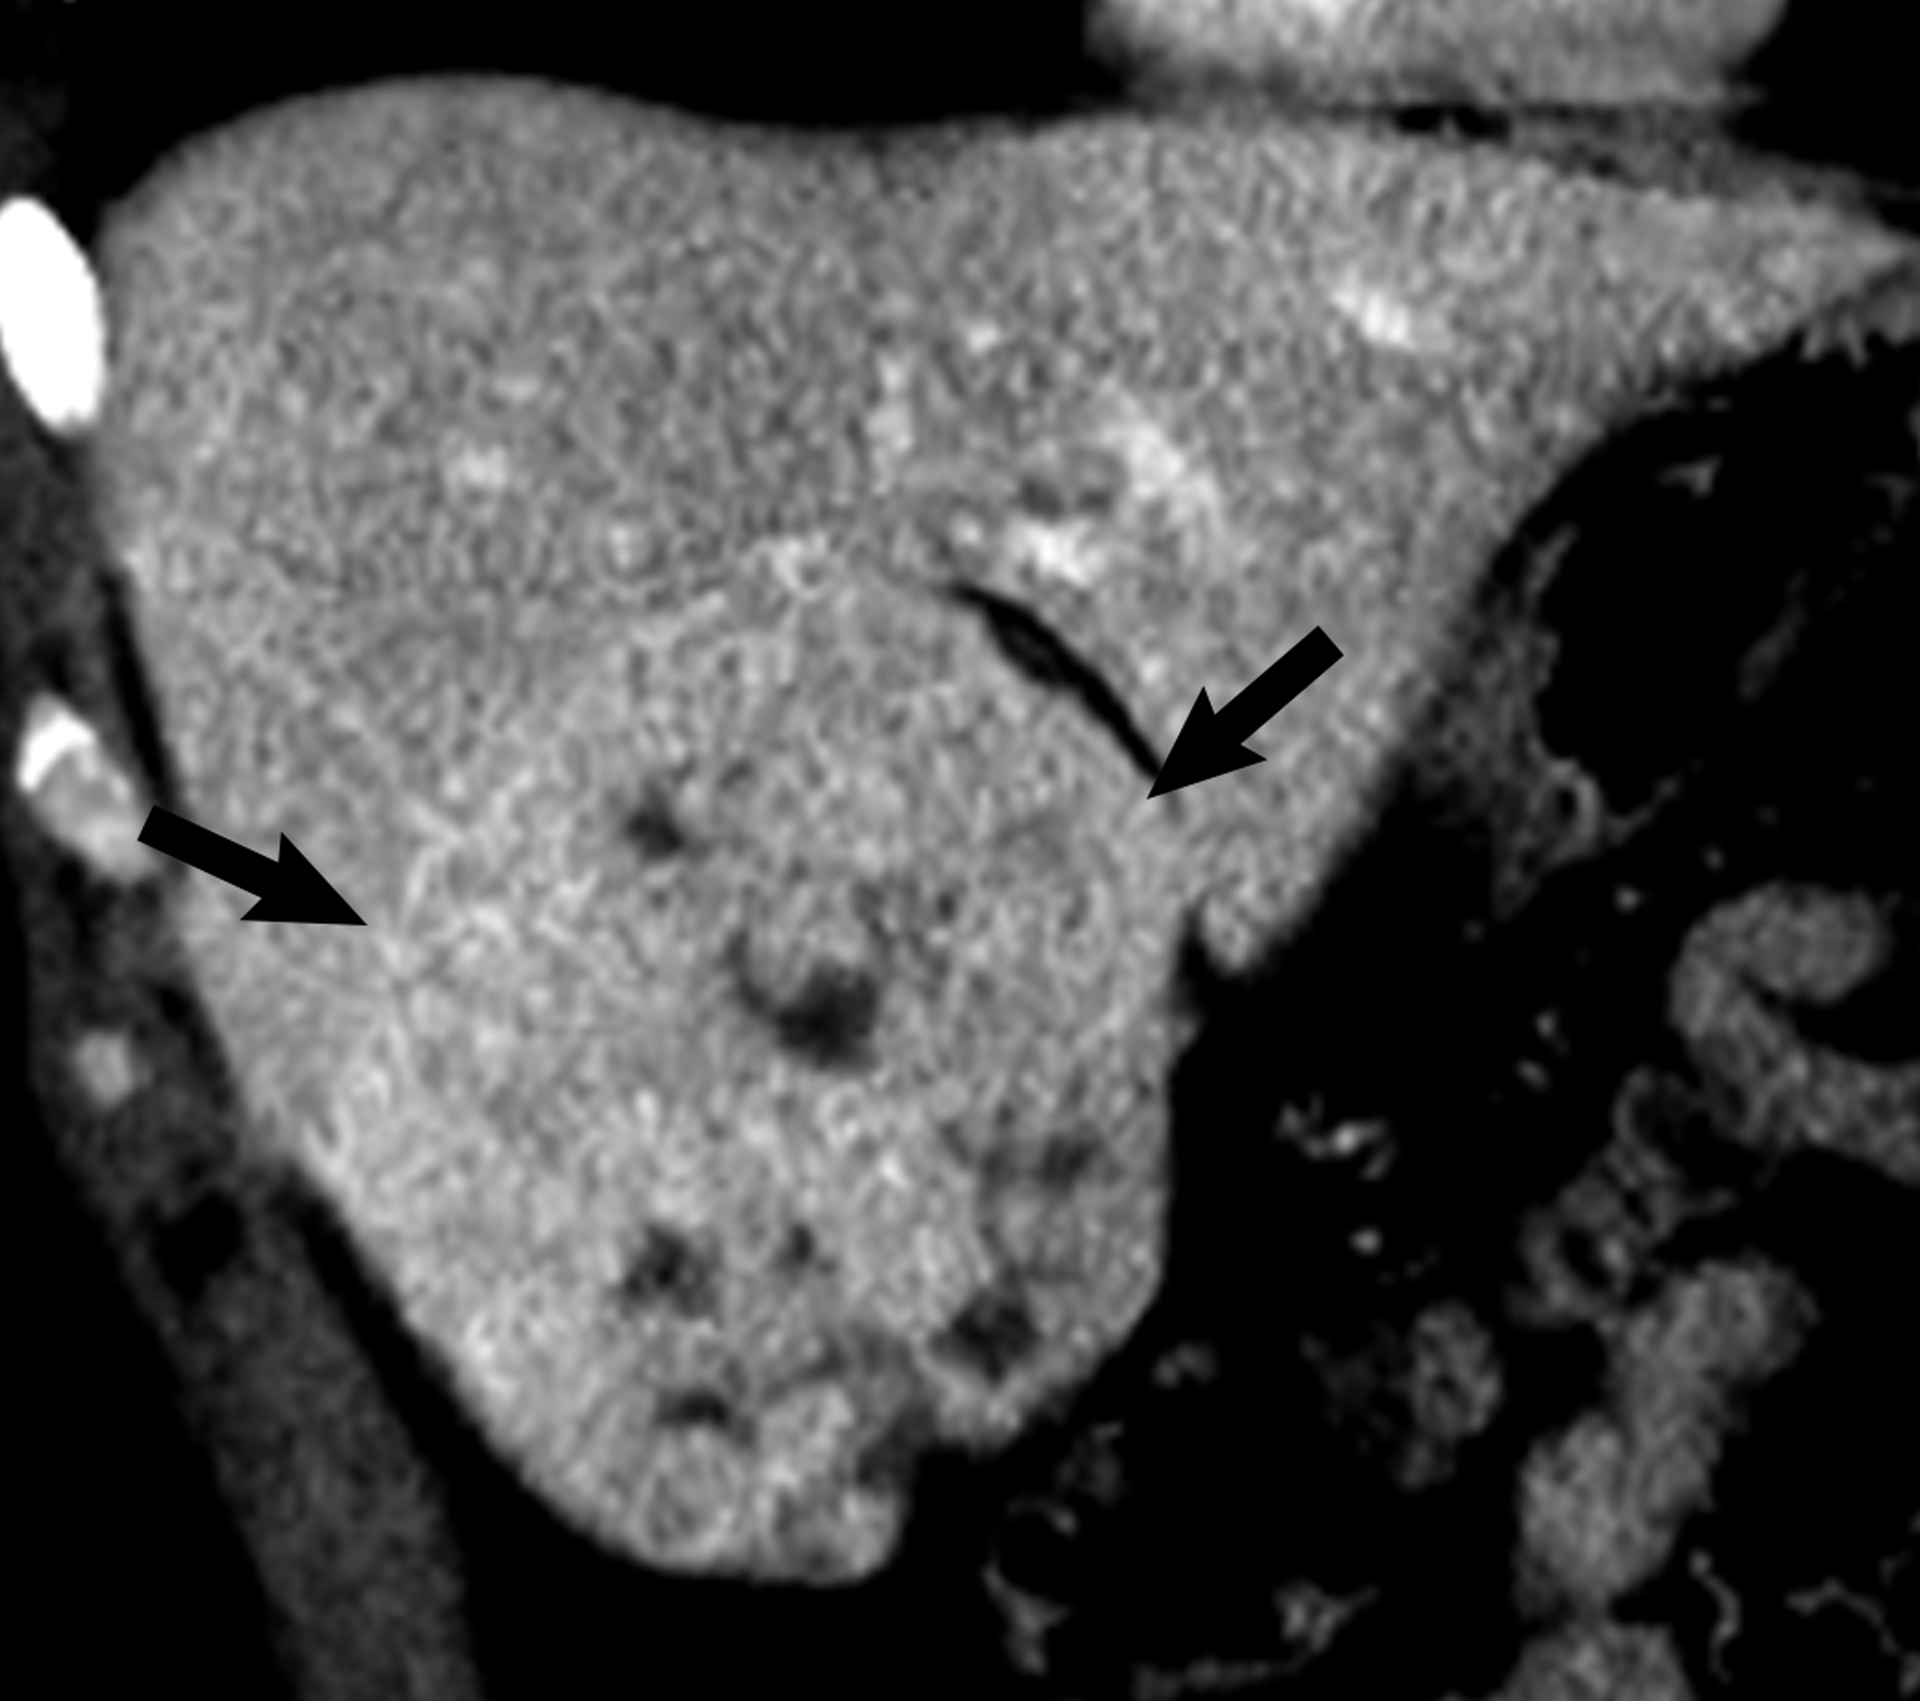

Figure 5.

26 year-old man with hepatocellular carcinoma. Coronal contrast-enhanced CT shows a 10.0 cm heterogeneously mildly hyper-enhancing liver mass (arrows). The mass was determined to be heterogeneous by both reviewers.

There were 37 heterogeneous observations (mean diameter 2.6 cm ± 17.9 cm) and 2 were clinically important (5.4%, 95% CI 0.7–18.2%). One observation was a 3.4 cm hepatic adenoma in a 42 year-old woman (Figure 4). The diagnosis was made by MRI with a hepatobiliary contrast agent. The other was a pathologically proven 10.0 cm HCC in a 26 year-old man with no risk factors for HCC (Figure 5). Fifteen heterogeneous observations were characterized with diagnostic imaging, of which 13 were hemangiomas, 1 FNH, and 1 hepatic adenoma. Sixteen were characterized with follow-up imaging, of which 7 had no growth, 6 decreased and 3 resolved. The remainder had clinical follow-up (n=4).

We found 2 clinically important lesions among 37 incidental heterogeneous hyper-enhancing liver observations (1 HCC and 1 adenoma). Both observations were large (3.4 and 10.0 cm) and thus size is likely an important factor in determining clinical importance. Most of the heterogeneous observations with diagnostic imaging (13/15) proved to be hemangiomas. These were likely hemangiomas that demonstrated some but not all of the required features of a typical hemangioma during the portal venous phase and therefore could not be diagnosed with confidence.